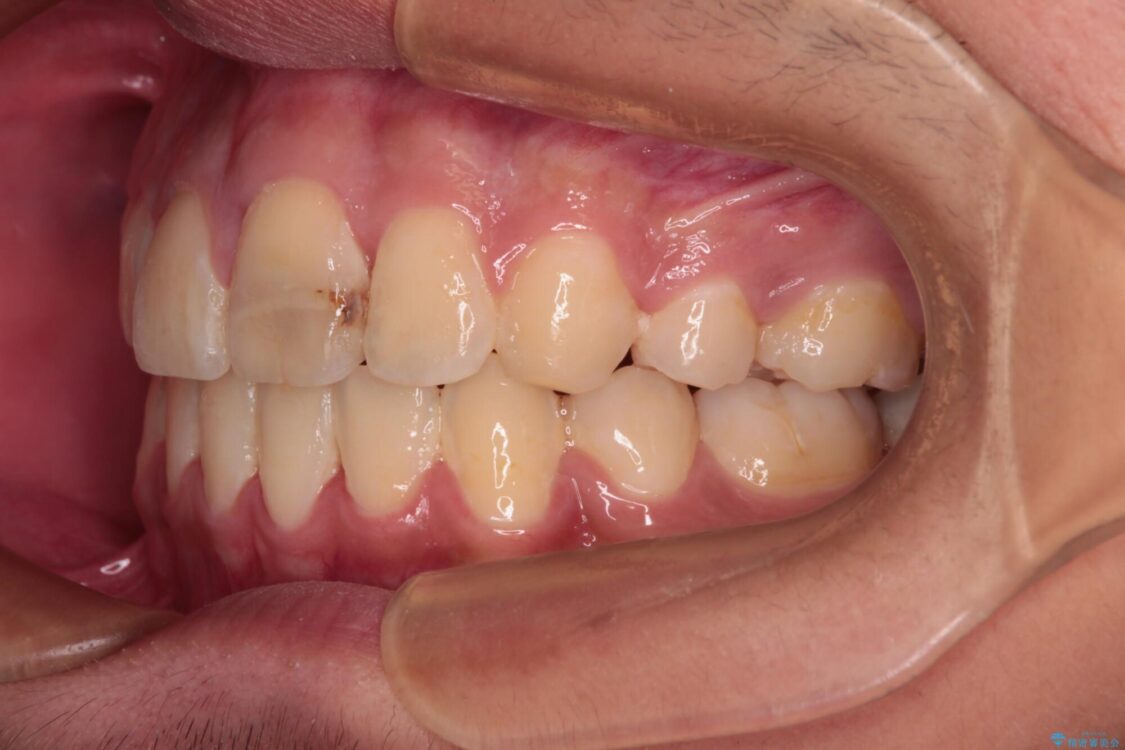

治療途中

• 膨らんだ口元 ワイヤー装置での抜歯矯正 治療途中画像